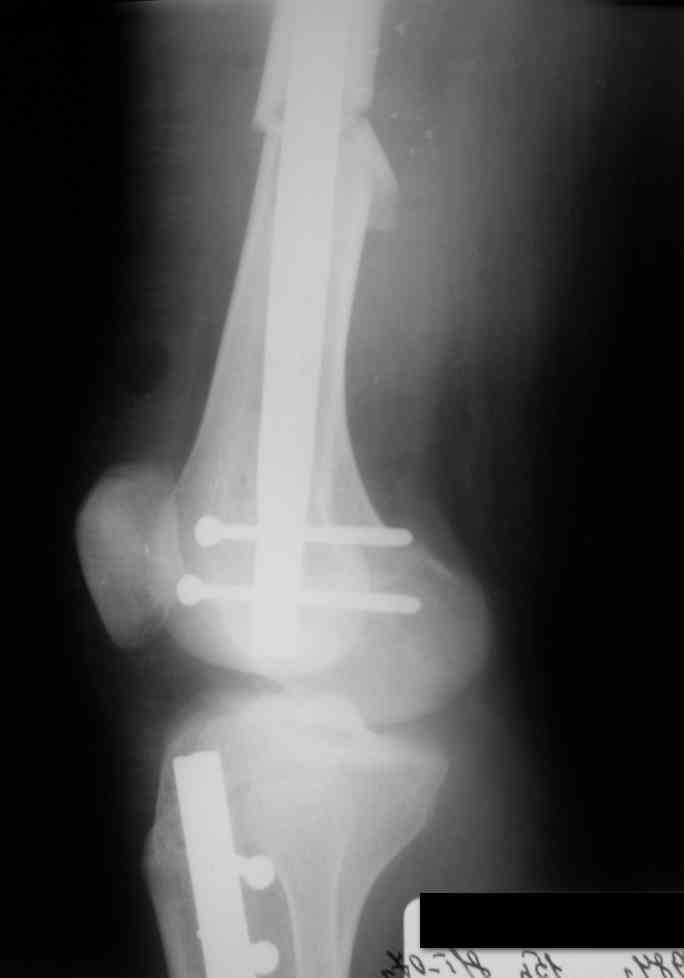

Дорогой Александр. Имею скромный опыт использования системы Fixion при переломах плеча, бедра и тибии. Всего 18 наблюдений с сентября 2006 г. Результаты отличные. Гвоздь индивидуален для каждого медуллярного канала. Легко имплантируется как в узкий, так и в деформированный канал. Это позволяет применять метод интрамедулярного остеосинтеза без ненужных потерь времени операции, флюороскопии и реально снижает крвопотерю и операционный риск. Удаление происходит без проблем. Особенно интересны больные с ипсилатеральными переломами бедра и голени.

> Особенно интересны больные с ипсилатеральными переломами бедра и голени.

Да, спасибо за интересные иллюстрации. Получилось очень симпатично. На большеберцовой кости непременно надо было винты? Там же был торцовый упор, перелом в средней трети?